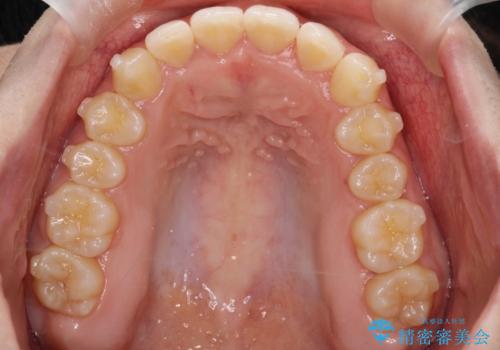

押しつぶされた歯列、アーチの拡大だけで非抜歯で改善した症例

初診時の歯並びの状態としては、上下ともに全体に及ぶの中等度以上のがたつき(叢生)があり、全額的に歯列のアーチが内側に押しつぶされた状態でした。

強い叢生がありましたが、抜歯は行わず上下顎ともに、主に歯列弓の拡大を行い叢生を改善しました。

矯正装置としてはマウスピースを使用しています。